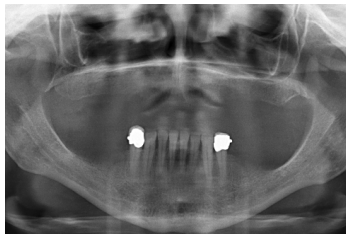

Para iniciar la fase de diagnóstico se realiza una radiografía panorámica que nos de una idea del estado general de ambos maxilares para iniciar el plan de tratamiento. En ella se ve como existe aparentemente altura en el reborde maxilar tanto a nivel anterior como posterior y un nervio dentario bajo en la mandíbula que nos permite tener una mayor cresta ósea residual disponible para la inserción de los implantes (Figura 3).

Cuatro meses después de la cirugía inicial de regeneración del maxilar se lleva a cabo un nuevo Cone-beam dental, en el que se planifica la siguiente fase de la cirugía en función de la ganancia ósea que se ha logrado con los injertos en bloque y la técnica de Split en dos fases. En las imágenes podemos observar como en las zonas de máxima atrofia, donde se colocan los bloques se ha logrado una anchura que triplica la inicial (Figuras 19 y 20). En la apertura del colgajo se observa como las imágenes del TAC de planificación se corresponden con la realidad, y además que la zona tratada mediante Split en dos fases ha logrado también una anchura de cresta que ahora permite la retirada de los implantes transicionales y la inserción de nuevos implantes en esta posición, con una mejor situación de partida y eje para la confección posterior de la prótesis (Figuras 21-22). Se procede a la inserción de los implantes y se realiza una prótesis provisional de carga progresiva apoyada en los implantes colocados en la primera fase quirúrgica. De este modo, la paciente puede tener una prótesis fija sobre implantes que servirá para ir dando forma a los provisionales en cuanto a estética y función de cara a la prótesis definitiva (Figuras 23-24).

Cuatro meses después se procede a la carga de los implantes insertados en esta segunda fase quirúrgica. De nuevo se opta por unas segundas prótesis provisionales de carga progresiva, elaboradas del mismo modo que las anteriores Tres meses después la oclusión está preparada para la confección de la prótesis definitiva, por lo que se transforma la prótesis en una prótesis metal-cerámica, atornillada sobre transepitelial confeccionada mediante cad-cam (Figuras 25-26). La paciente ha recuperado la función demandada, así como la corrección de la oclusión de la prótesis completa, que presentaba una mordida cruzada lateral derecha con disminución de la dimensión vertical al inicio del tratamiento. La paciente acude a sus revisiones y el tratamiento se mantiene estable tal como se muestra en las imágenes tomadas a los 10 años de seguimiento (Figuras 27-28).